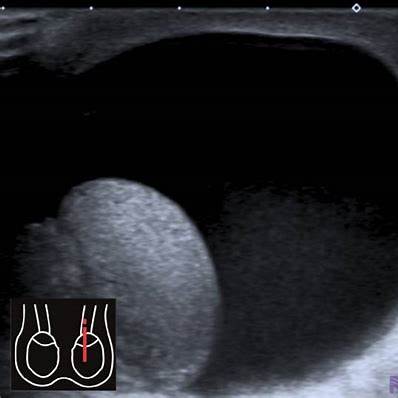

진단

• 촉진 및 시진 (빛 비추기(transillumination) 검사 — 빛을 비췄을 때 투과되는 정도 확인)

• 초음파 검사로 액체 저류, 고환 및 주변 구조 이상 유무 확인 (예: 고환 종양, 고환염 동반 여부 등).